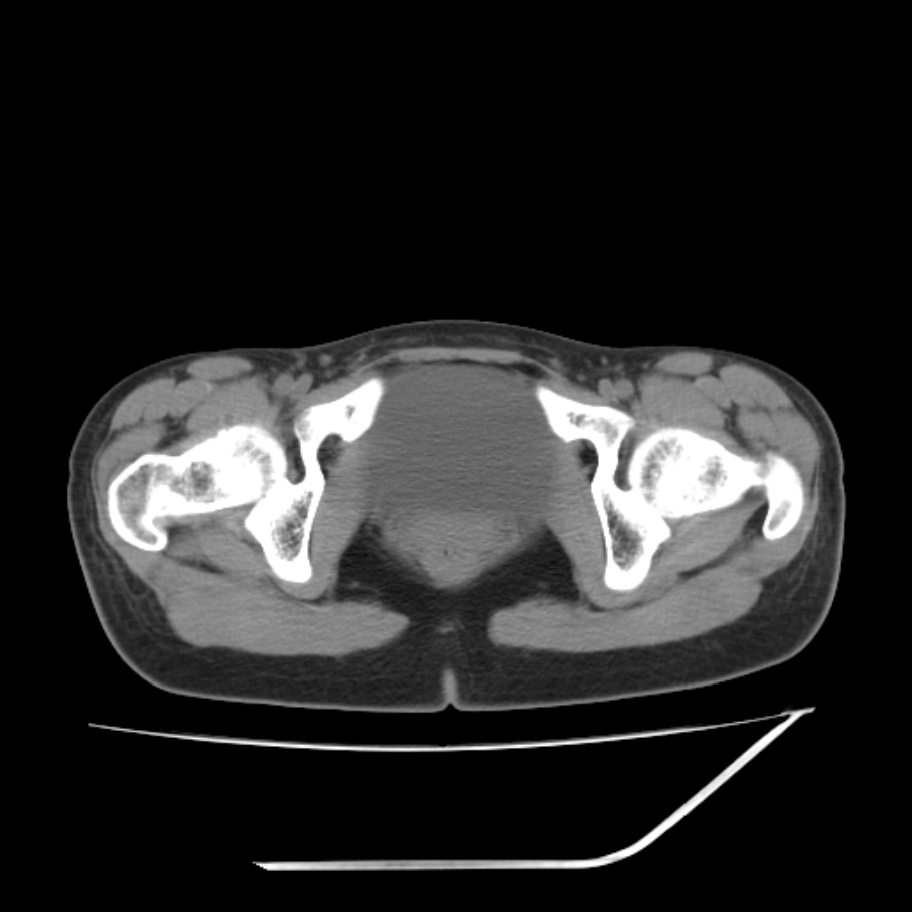

女,25岁。偶尔有右下腹不适感,余无明显异常。(结婚半年),囊壁较厚,是卵巢囊肿吗?

右侧卵巢区椭圆形囊性肿物,内壁光滑 无分隔。直肠子宫间隙内有少量积液征象。结合临床考虑卵巢巧克力囊肿,还要问问有没有痛经,本例ct怎么没有灌肠?要是灌肠或前一前口服造影剂,起码可以和肠管区别开

右侧囊性占位,1囊肿,2囊腺瘤。

考虑右侧卵巢囊性占位性病变(巧克力囊肿?),盆腔积液有不排除宫外孕可能,请结合临床和b超。

右侧卵巢囊伴盆腔少量积液。